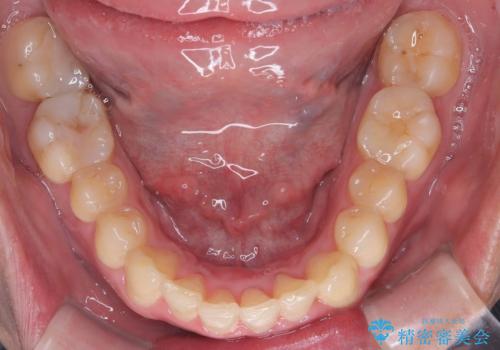

- 「上の前歯の捻じれと下の前歯のでこぼこを治したい」を主訴に来院された患者様です。

矯正検査の結果、非抜歯で矯正可能だったためインビザラインで治療を行いました。

アーチの拡大とIPRで叢生を改善いました。

11ヵ月で矯正を終える事ができ患者様も大変ご満足されていました。